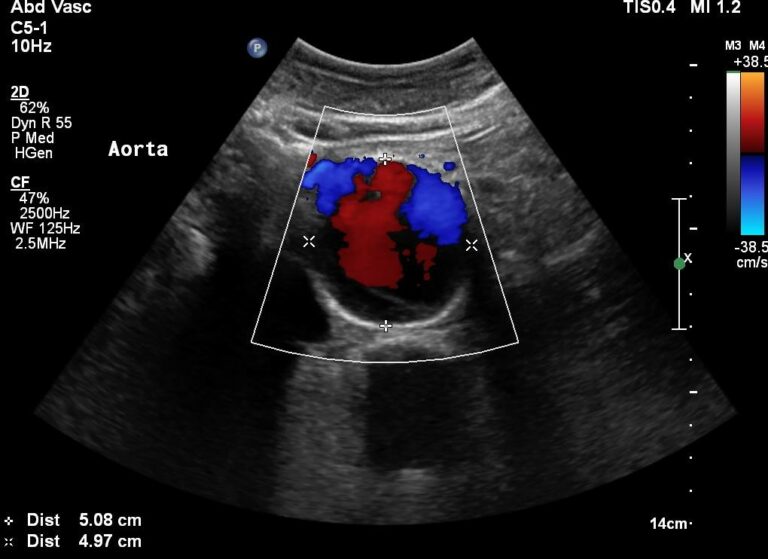

TRIPLEX ΑΓΓΕΙΩΝ

TRİPLEKS GEMİLER

TRIPLEX OF VESSELS

ABDOMINAL ULTRASOUNDS

ΥΠΕΡΗΧΟΙ ΑΝΩ-ΚΑΤΩ ΚΟΙΛΙΑΣ

KARIN ULTRASONLARI